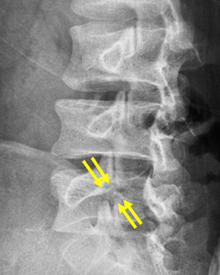

矢印が分離部で骨が離れています。

分離部に骨が移植され骨癒合が

得られています。